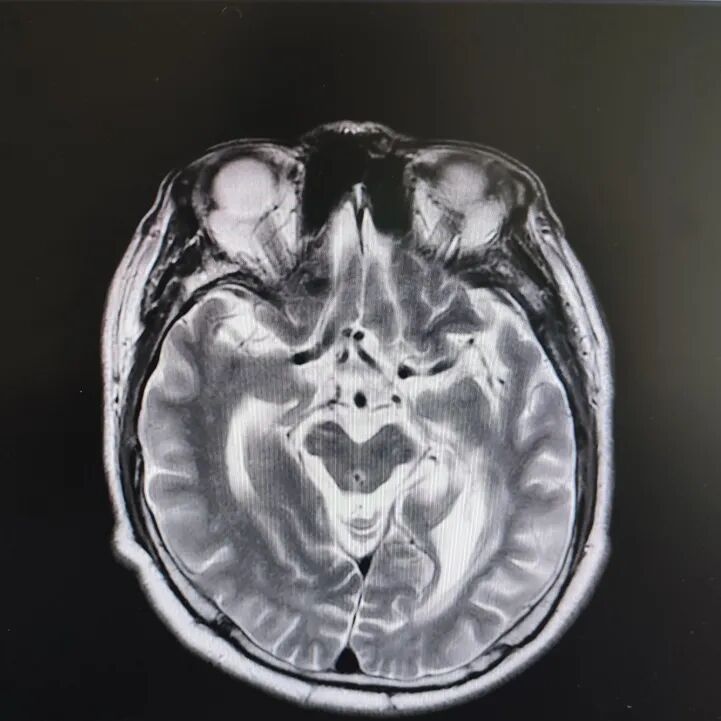

病房里還有另一位患者,來的時候情況更讓人揪心:反應遲鈍,表情呆滯,行動緩慢。頭顱核磁顯示腦萎縮明顯,但查體發(fā)現肌張力、計算力、記憶力、定向力均正常,不符合典型血管性癡呆或阿爾茨海默病表現。

患者頭部磁共振影像

憑著多年診治疑難雜癥的豐富經驗,趙主任敏銳地意識到這“癡呆”可能是假象,背后另有隱情。他果斷建議進一步做特殊感染篩查。果然,檢查證實這位患者同樣是感染了蒼白密螺旋體!經過精準的抗感染治療,奇跡發(fā)生了:患者的反應變快了,眼神靈活了,走路也恢復了正常步態(tài)。最終的診斷是“麻痹性癡呆”——一種由神經梅毒引起的、可治療逆轉的“癡呆”類型!